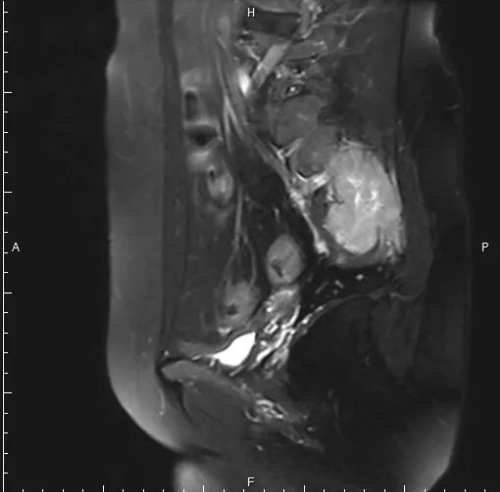

患者韩某,女,49岁,一个多月前,不明原因出现腰骶部疼痛,难以忍受,骶尾部及左侧臀部压痛,左侧臀部及会阴部感觉减弱,口服镇痛药洛索洛芬钠片对症治疗,不见好转,随后就诊于我院,医生查骨盆MRI示:骶椎左侧占位性病变。

经神经外科程主任细致查体,结合患者症状与影像学表现,与王教授制定了详细的手术方案,拟于显微镜下行骶椎左侧占位切除术,术中彻底清除肿瘤以及被侵蚀的骨性组织。术后患者症状明显好转。